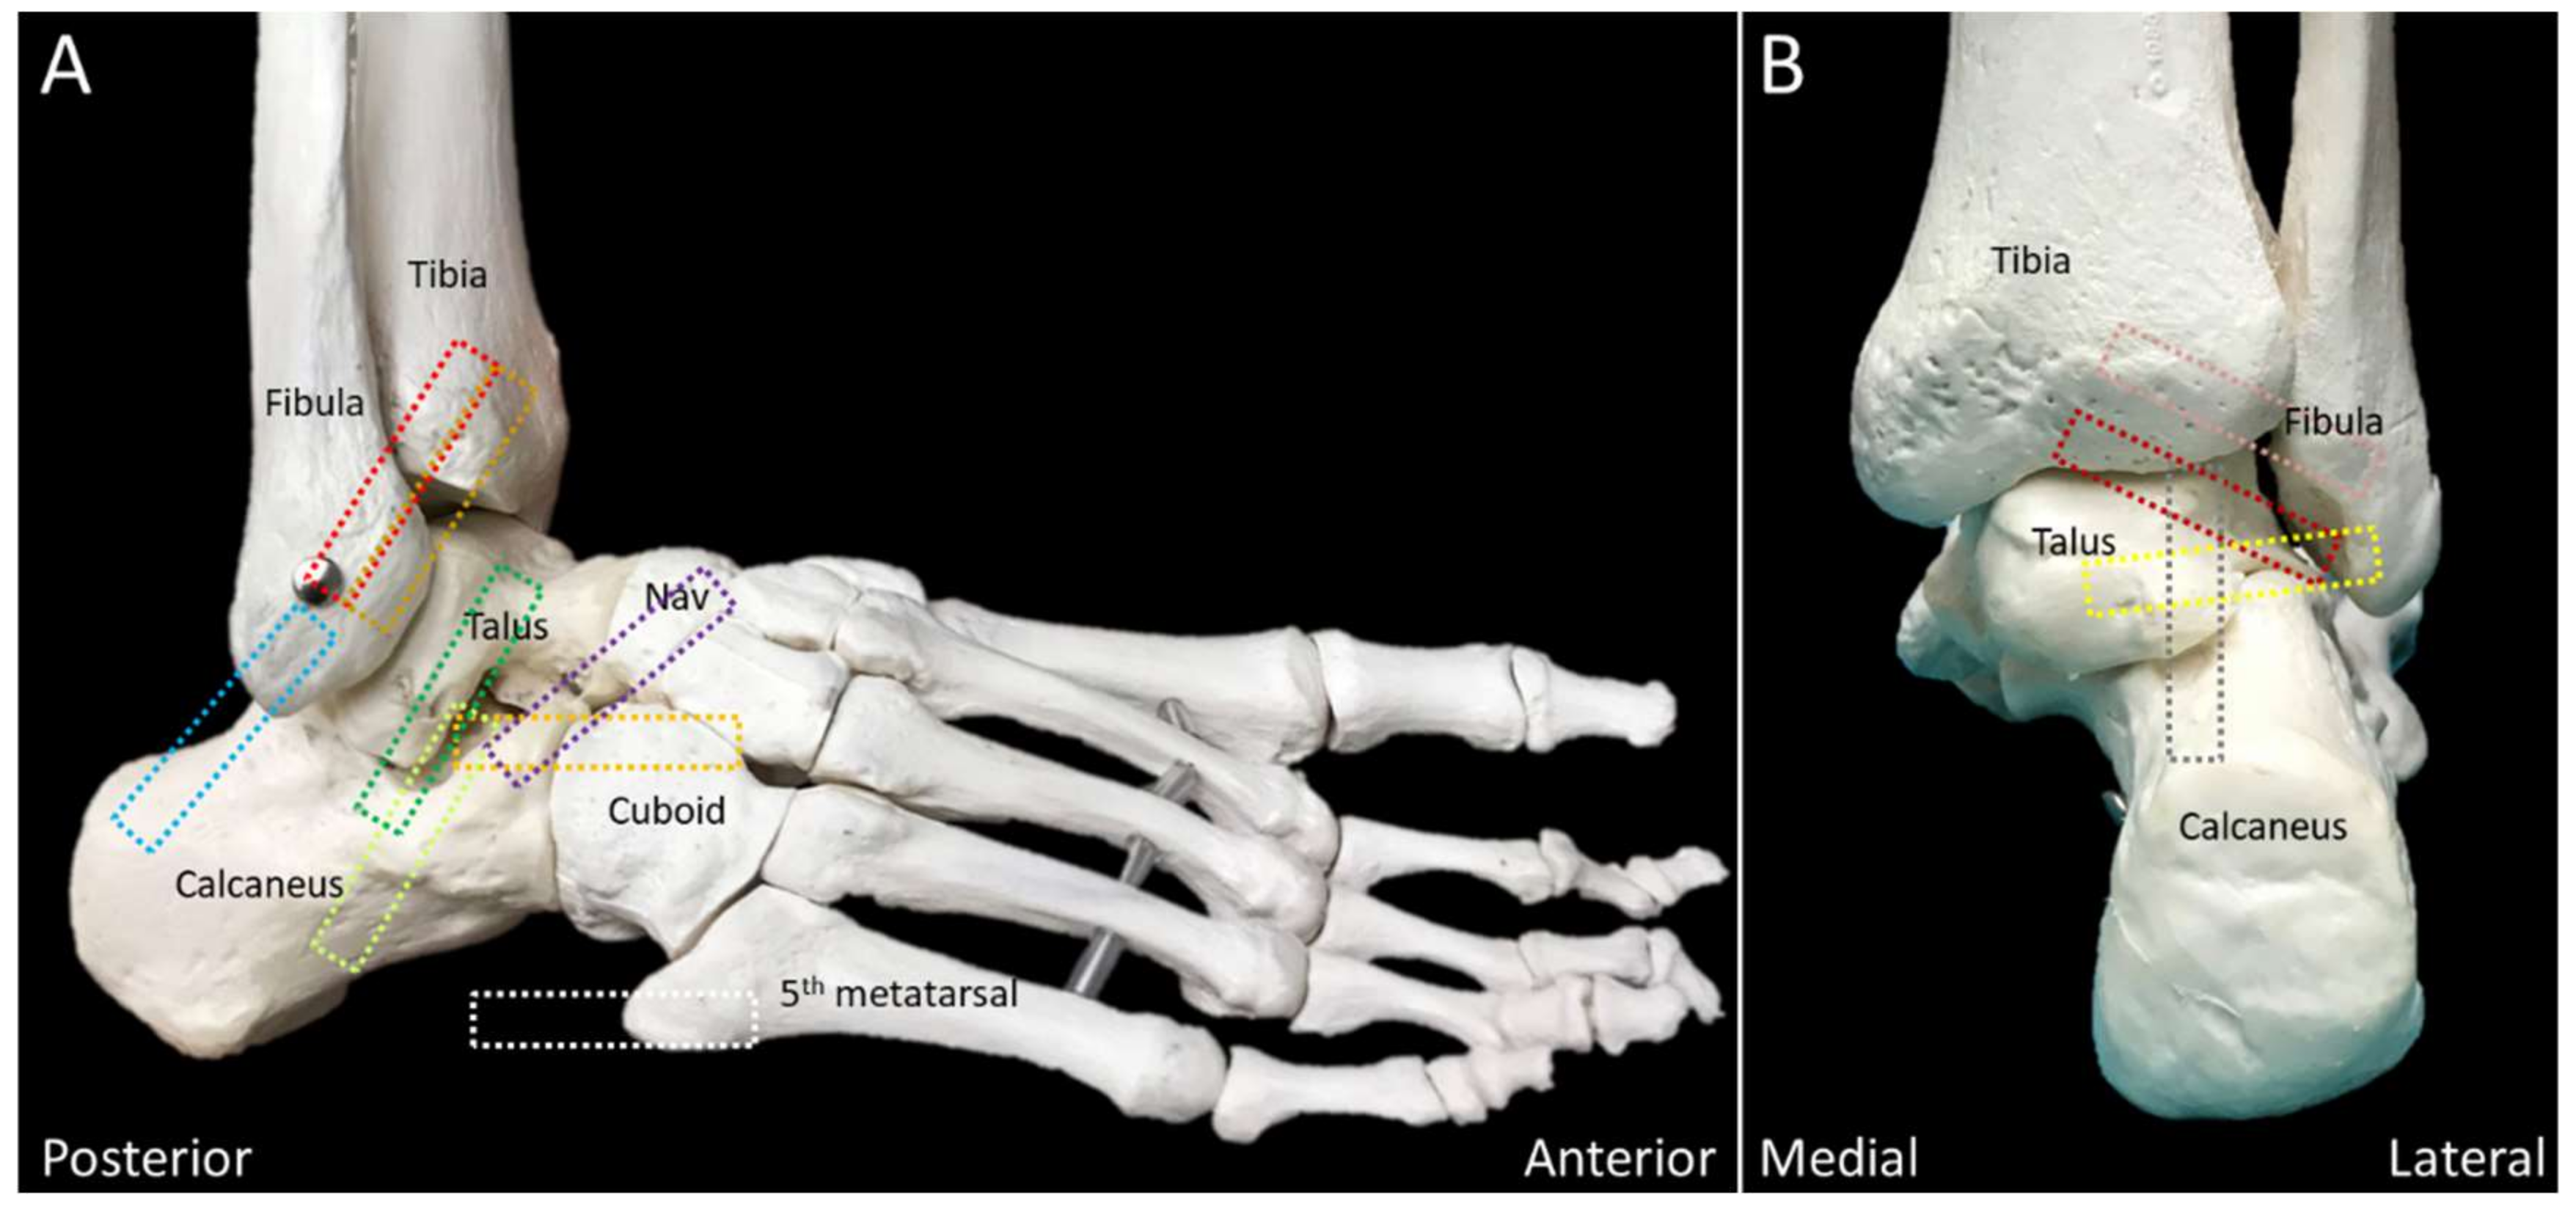

2.5. Lateral Talocalcaneal Ligament

2.5.1. Anatomy

2.5.2. Scanning Technique

2.5.3. Clinical Relevance

2.6. Bifurcate Ligament

2.6.1. Anatomy

2.6.2. Scanning Technique

2.6.3. Clinical Relevance